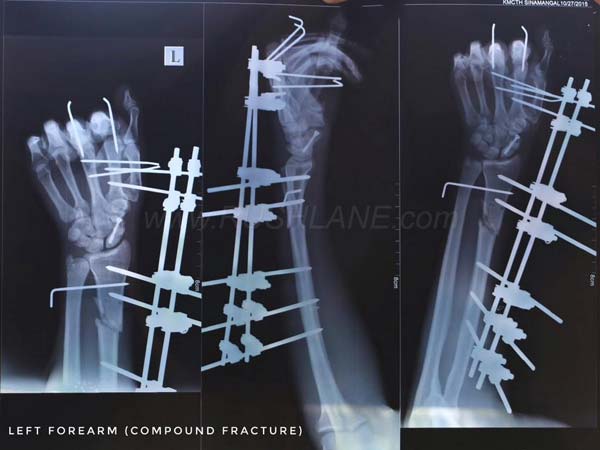

अस्पताल में एक्स-रे स्कैन से पता चला कि इस हादसे में सुकदेव के शरीर की 18 हड्डियां टूट चुकी हैं। इसमें उनके दोनों पैरों में कई फ्रैक्चर थे। हाथ, छाती और पूरी शरीर में कई फ्रैक्चर हुए। सर्जरी करने वाले डॉक्टर्स ने तो यहां तक कह दिया कि अब यह कभी जिम नहीं जा पाएगा।

दुर्घटना के 3 महीने बाद, सुकदेव फिर से अपने पैरों पर खड़े हुआ। यह उसके लिए चलने सीखने का समय था। यह एक दर्दनाक प्रक्रिया थी क्योंकि धातु के प्रत्यारोपण उसके घुटनों और पैरों में किए गए थे। वे बड़े सुइयों की तरह थे और हमेशा पैरों को चोट पहुंचा रहे थे।